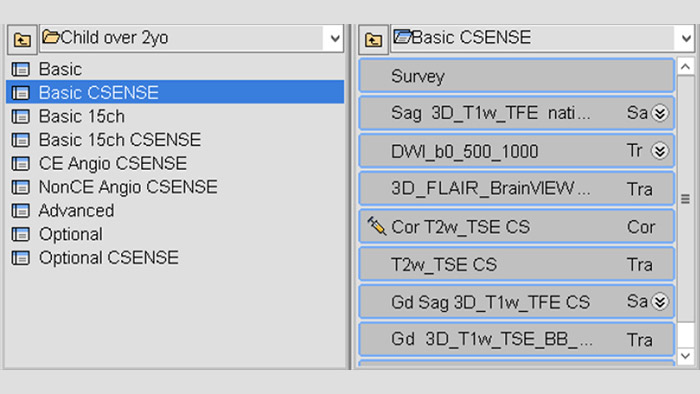

Robust ExamCards with flexibility to tailor

Having a collection of dedicated ExamCards is important, as these are the starting points of MRI examinations. “We begin every examination with one of the ExamCards from our collection,” says Dr. Junge. “Then during the examination, as new clinical questions arise based on the initial findings, we adjust and add sequences. This flexible way of working – ExamCards for the routine scans and the possibility to change a parameter with one click – I think that’s an great benefit of Philips MRI scanners.”

“Our application specialist initially helped us make our set of ExamCards for pediatric targets, which we built by adjusting the ExamCards from the standard set of Ambition. Each ExamCard bundles the sequences for a specific examination. Currently, we are still developing more ExamCards for the different age and size categories of our pediatric patients.”

"This flexible way of working – ExamCards for the routine scans and the possibility to change a parameter with one click – is an great benefit.”

Dedicated pediatric oncology ExamCards

An extensive set of dedicated pediatric ExamCards was developed in a collaboration with some expert users in Germany and based on the guideline from the European Society for Pediatric Oncology Brain Tumor Imaging Group (Nov 2017) and consensus of 11 German Philips MRI users (March 2019). Some highlights are:

Neuro-oncology ExamCards for 3.0T

Body-oncology ExamCards for 1.5T

Examples of 3.0T neuro-oncology ExamCards (left) and 1.5T body-oncology ExamCards (right) for a selected age group. The list of sequences from the highlighted ExamCard is shown on the right. These ExamCards are part of the Philips DACH Pediatric Reference Scan Protocols